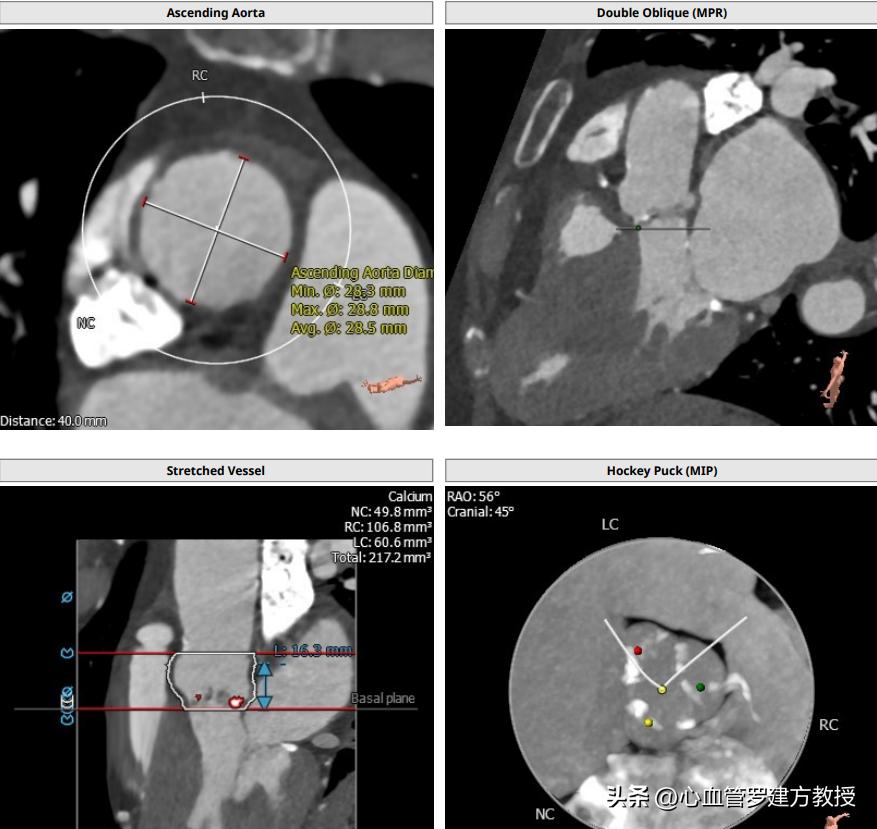

病人女,64岁,2018年在广东省人民医院行TAVR手术,三叶瓣,轻度钙化,瓣环20.5,Lvot 20.6,左右冠高度尚可,STJ 24.2,窦部长短径分别为26.3及23.3,窦部空间相对较小,结合术中球扩结果,瓣膜冠脉风险不高,遂植入VenusA 26号瓣膜。